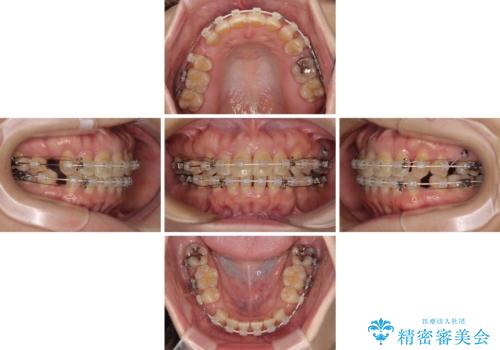

- 矯正装置

- 審美装置

- 2年6ヶ月

- 10-30回